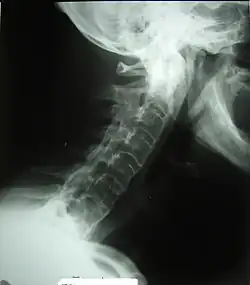

![]() Columna vertebral anquilosada. Se produce una fusión de las vértebras afectadas. | ||